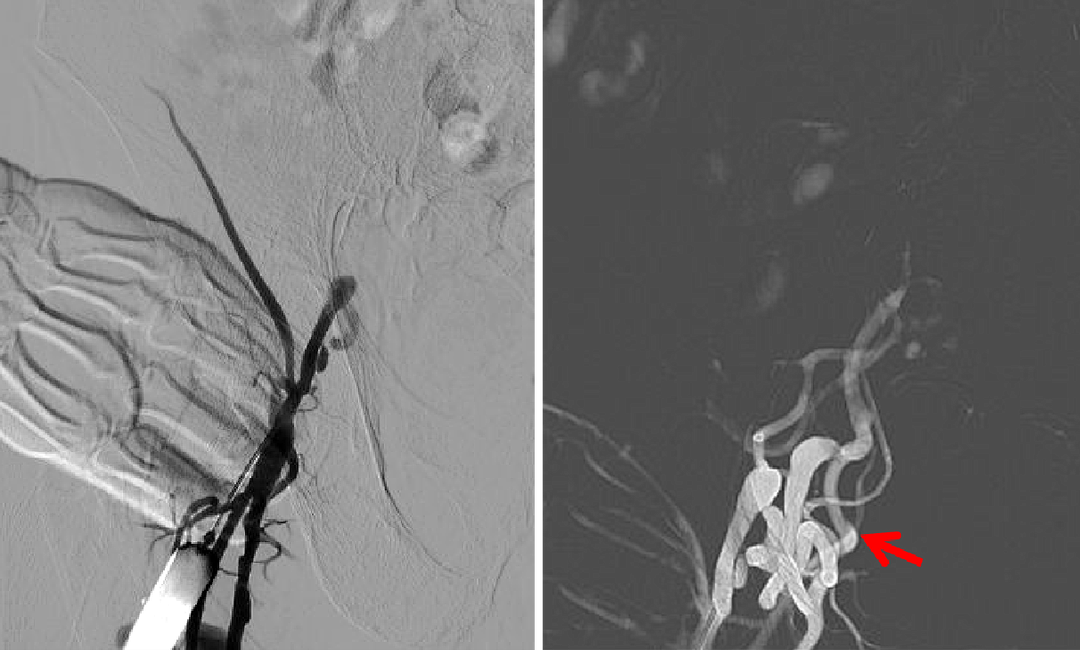

右侧股动脉穿刺针造影发现股动脉周围畸形血管团,入路困难

经右桡动脉穿刺上肢路图造影